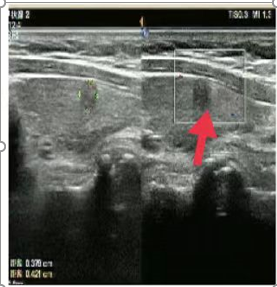

07、**女士,55岁

于2023年11月2日在邯郸仁泰北区体检,甲状腺彩超检查提示: 甲状腺右叶见大小约0.4*0.25cm低至无回声,边界清晰,CDFI:其内及周边未见血流信号。左叶见多个等低回声,较大约0.37*0.42cm,较大纵横比>1,边界尚清,CDFI:其内及周边未见血流信号。2023年11月3日电话通知客户到三甲医院进一步检查。2023年11月20日跟踪回访,客户已在邯郸某三甲医院穿刺,诊断甲状腺癌后完成手术切除。